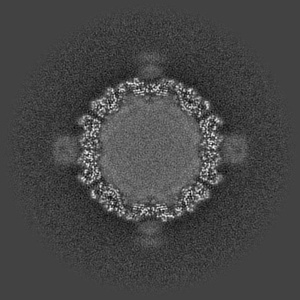

Cryo-EM structure of coxsackievirus A16 mature virion in complex with Fab h1A6.2

Single-particle3.69 Å

Sample: Coxsackievirus A16 mature virion in complex with Fab h1A6.2

Broadly therapeutic antibody provides cross-serotype protection against enteroviruses via Fc effector functions and by mimicking SCARB2.

(2024) Nat Microbiol , 9 , 2939 - 2953